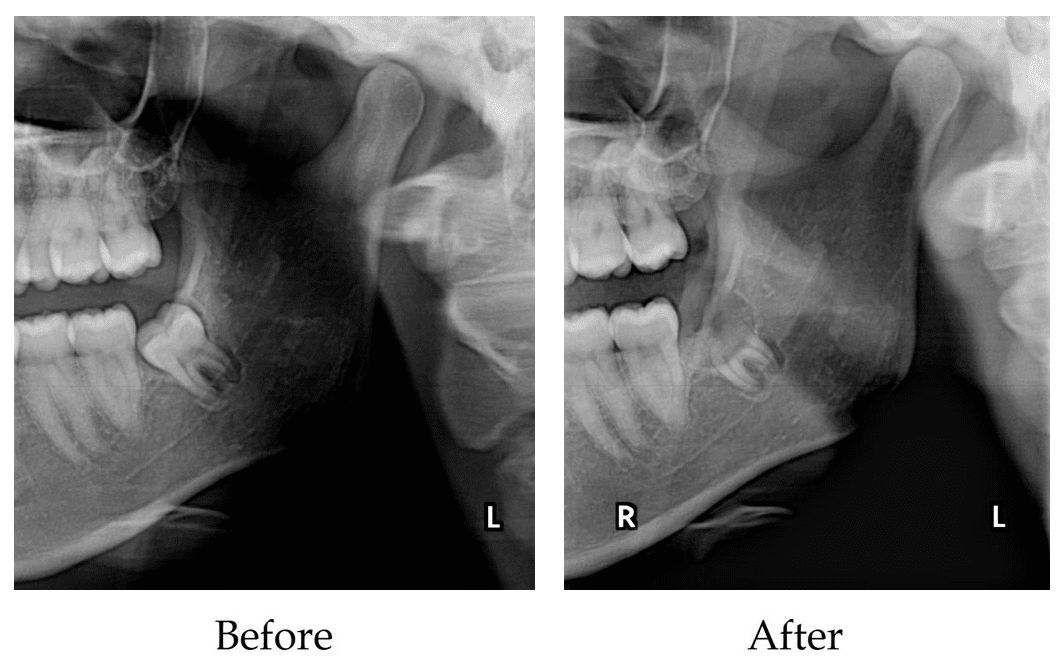

This is the most common situation when surgical protocol is used for extraction. This does refer to the wisdom teeth that are fully or partially impacted in the jaw bone.

Because of the lack of space, wisdom teeth can sometimes emerge at an angle or get stuck and only partially emerge. Wisdom teeth that grow through like this are known as impacted.

In this instance the the wisdom tooth can be removed completely or in cases of high risk of nerve injury only the crown of the wisdom tooth can be removed (coronectomy).